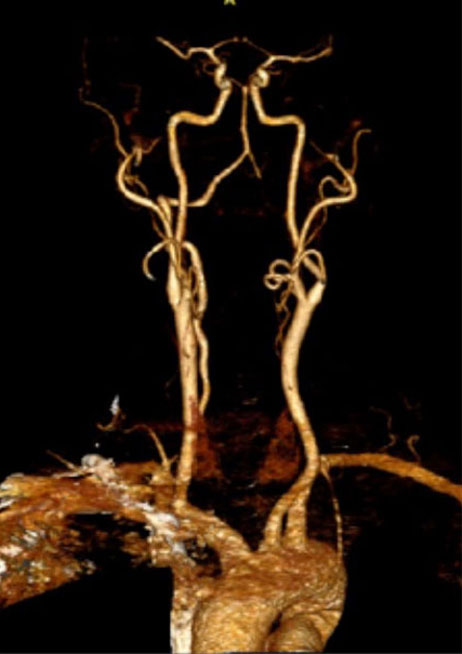

CTA of the neck and brain reveal that the left Vertebral Artery is completely occluded at approximately the C1-C2 level with extensive hypertrophic degenerative osseous changes from C1-C3. Retrograde flow into the post PICA left Vertebral Artery is observed from the co-dominant right Vertebral Artery which appears to be the primary supply into the basilar circulation. No significant Posterior Communicating arteries are observed on either the right or left Carotid Artery on the CTA imaging (Figure 1).

Dynamic provocative fluoroscopy failed to reveal significant Vertebral osseous instability (Figure 2A), however, Transcranial Doppler Flow velocities in the distal right Vertebral and Basilar Artery are markedly reduced during Extension of the Neck (Figure 2B).